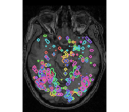

face

vs house

TV-l1

Graph-net

Social sparsity

Finally, an important aspect of the brain decoders is whether they segment well the brain regions that support the decoding. Such a question is hard to validate, yet there is evidence that TV- is a good approach [5]. Fig. 2 displays the decoder maps for the object-recognition tasks. For these tasks, we expect prediction to be driven by the functional areas of the visual cortex [27]. Indeed, the maps outline regions in known visual areas. The graph-net maps are much more scattered and less structured than the others. Conversely, the social sparsity maps are sparser and outline a smaller number of clusters.